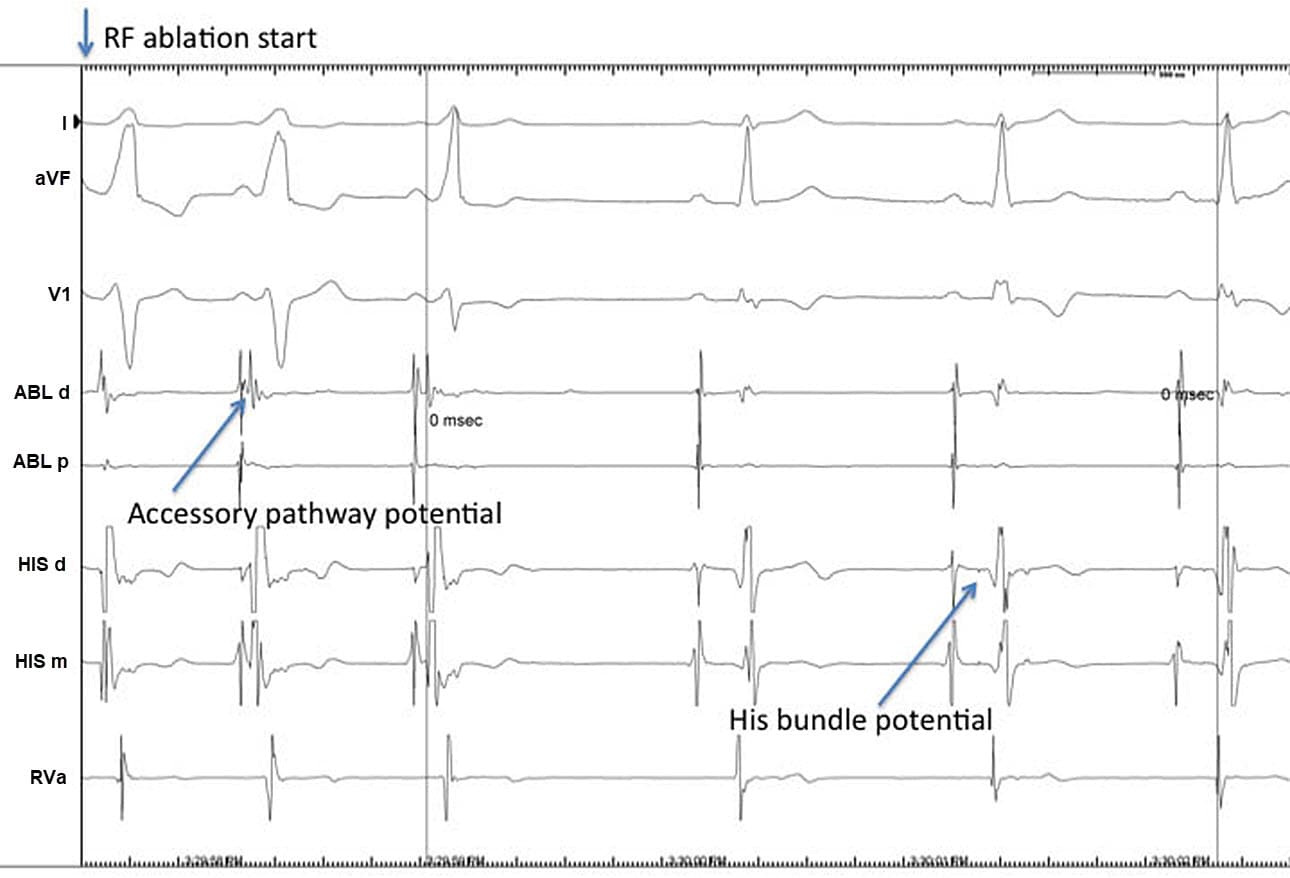

Sudden Cardiac Death

www.netterimages.comSudden Cardiac Death

www.netterimages.comSudden Cardiac Death

Sudden Cardiac Death

reference.medscape.comSudden Cardiac Death

reference.medscape.comSudden Cardiac Death